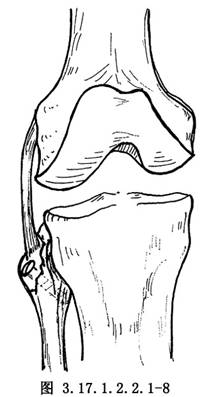

如半月板和交叉韌帶有損傷,儘可能予以修補,然後再自後側開始修補外側結構。①如有後外側關節囊撕脫,將其牽到脛骨關節面下方,用圓針引絲線穿過脛骨關節面下的鑽孔,由前到後縫合固定在脛骨上(圖3.17.1.2.2.1-4)。固定前將脛骨附着部的骨表面弄毛糙,或用骨刀做一新鮮骨創面,以保證後外側關節囊的固定。②有膕肌腱撕裂者,按損傷類型採用不同的方法。股骨附着部的膕肌腱撕裂,常伴有外側副韌帶自股骨上撕脫,可採用Bunnell縫合,通過股骨的鑽孔,捆紮在股骨內上髁的骨面上(圖3.17.1.2.2.1-5)。膕肌腱本身撕裂,將兩端用Bunnell縫合(圖3.17.1.2.2.1-6)。撕裂在肌肉內或肌腱連接部,用Bunnell縫合通過脛骨前外側近端Gerdg結節的骨孔,將肌腱附着到脛骨的後面(圖3.17.1.2.2.1-7)。③修補外側副韌帶。對外側副韌帶的撕裂先明確撕裂的部位,對股骨附着部的撕脫可採用U形釘、螺釘固定,或將斷端用Bunnell縫合,通過股骨的鑽孔捆紮在股骨內上髁上。外側副韌帶從腓骨頂點撕裂則伴有股二頭肌腱、弓狀韌帶及腓側副韌帶附着點的複合撕脫,應一併修復,在腓骨頭穿孔,粗線縫合固定。伴有骨片撕脫,可用1枚螺釘或交叉克氏針固定骨片(圖3.17.1.2.2.1-8)。如爲韌帶本身的撕裂,找出兩斷端拉緊後屈膝30°位,用不吸收的絲線對端或重疊縫合(圖3.17.1.2.2.1-9)。並將外側緣向前推進,縫合在外側正中關節囊的後緣和外側副韌帶的後緣。還可應用股二頭肌腱、腓腸肌腱和髂脛束加強修補。